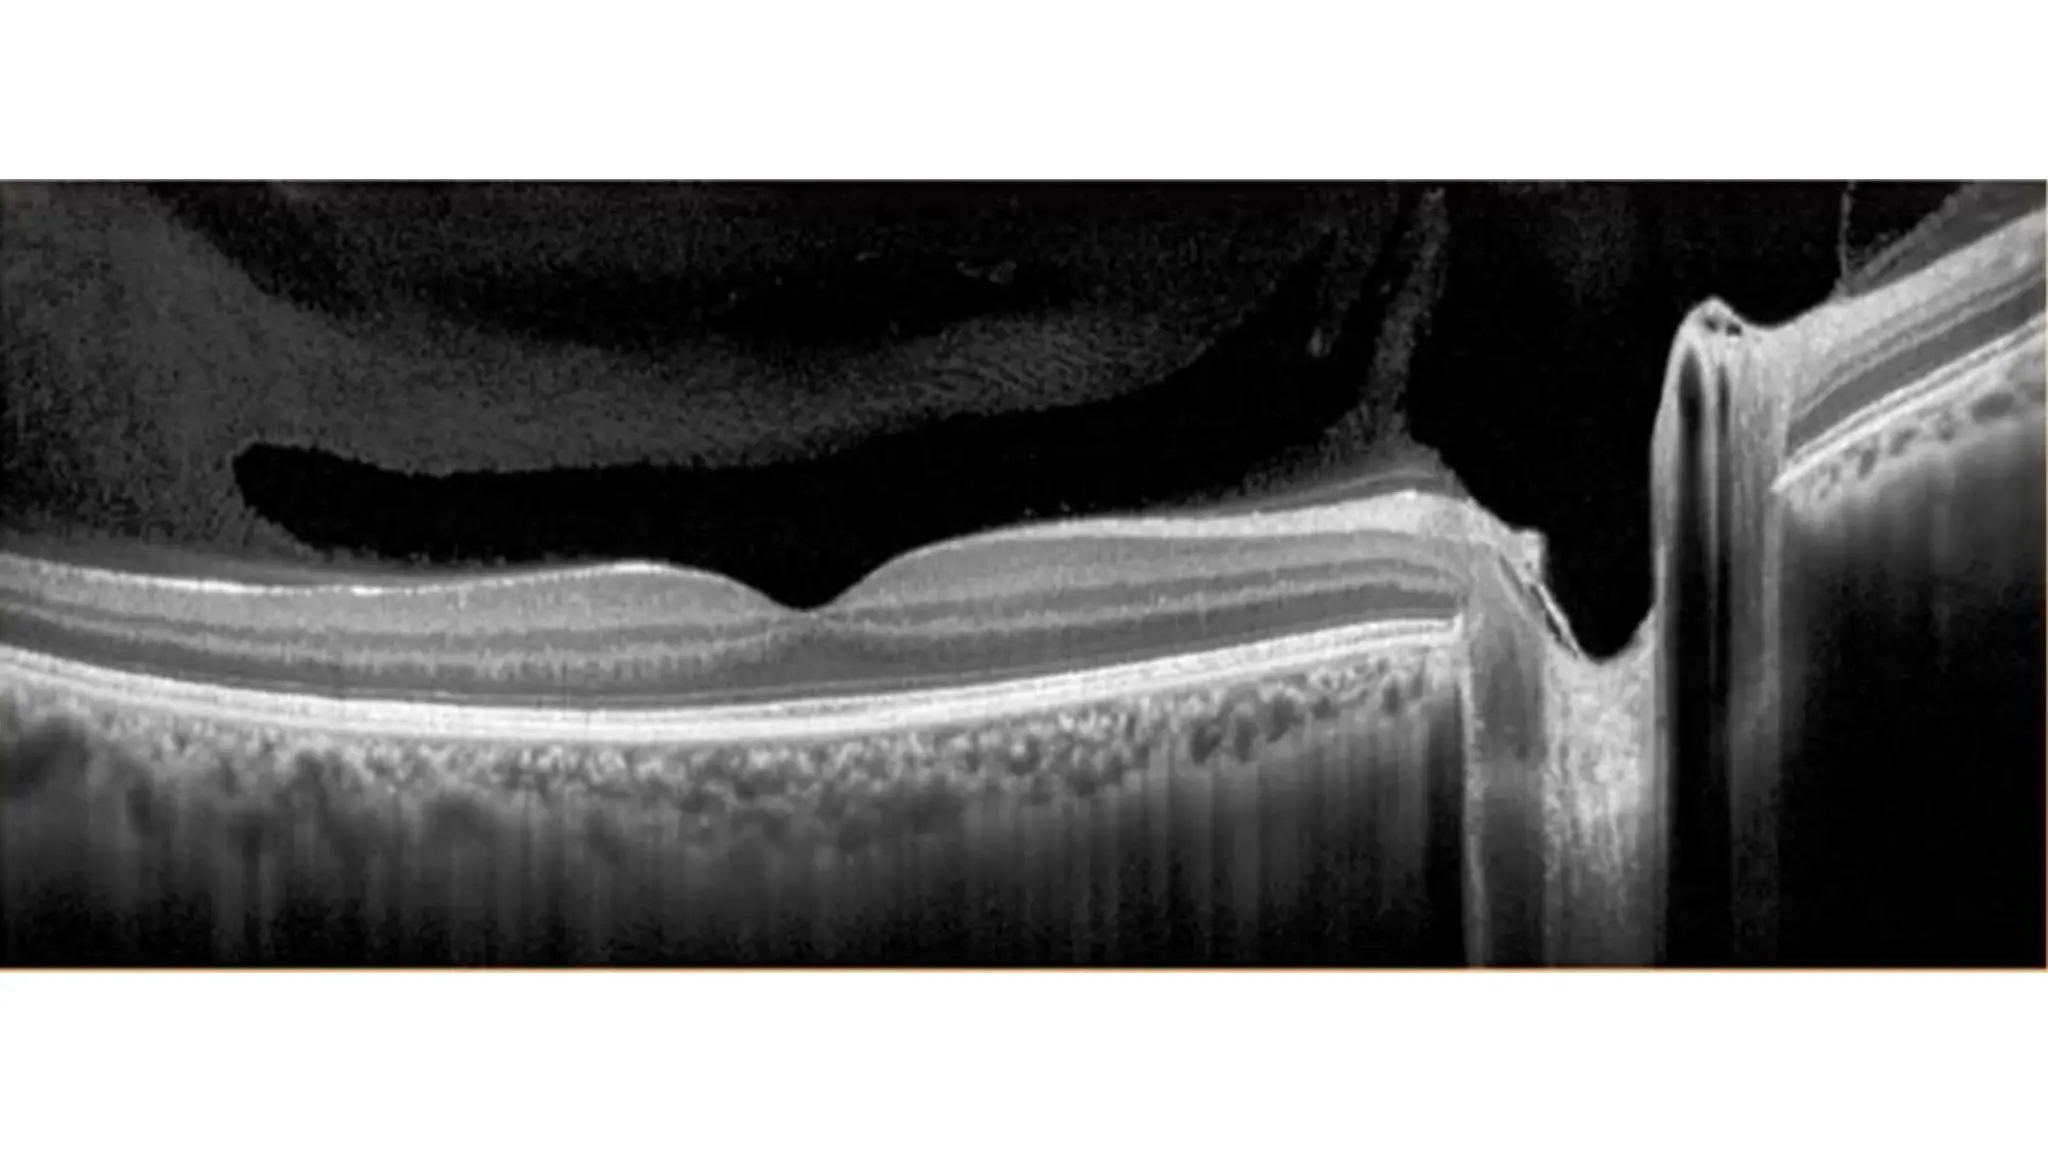

The document discusses various stages of posterior vitreous detachment (PVD) and associated ophthalmological conditions. It highlights the classification of PVD stages, including no PVD, paramacular PVD, and complete PVD, alongside related factors like traction and retinal issues. Key acronyms and terms relevant to diabetic retinopathy and retinal morphology are also mentioned.